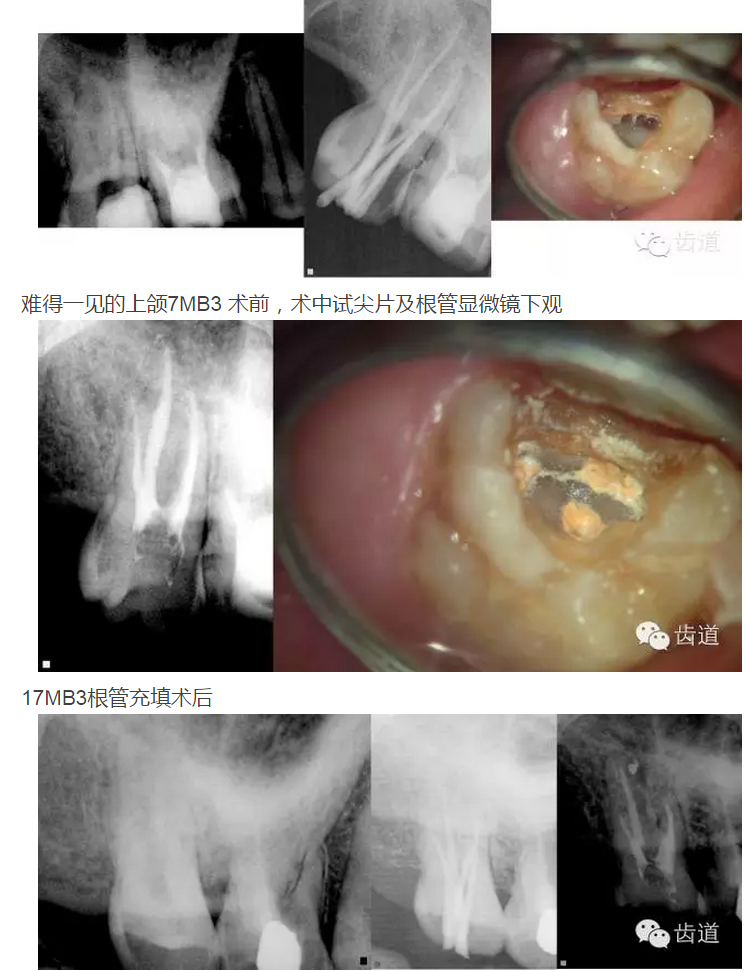

上頜第一磨牙:多為3-4個根管,MB2發(fā)生率約為60%;

上頜第二磨牙:與上頜第一磨牙相似,多為3根管,偶見雙鄂根管;